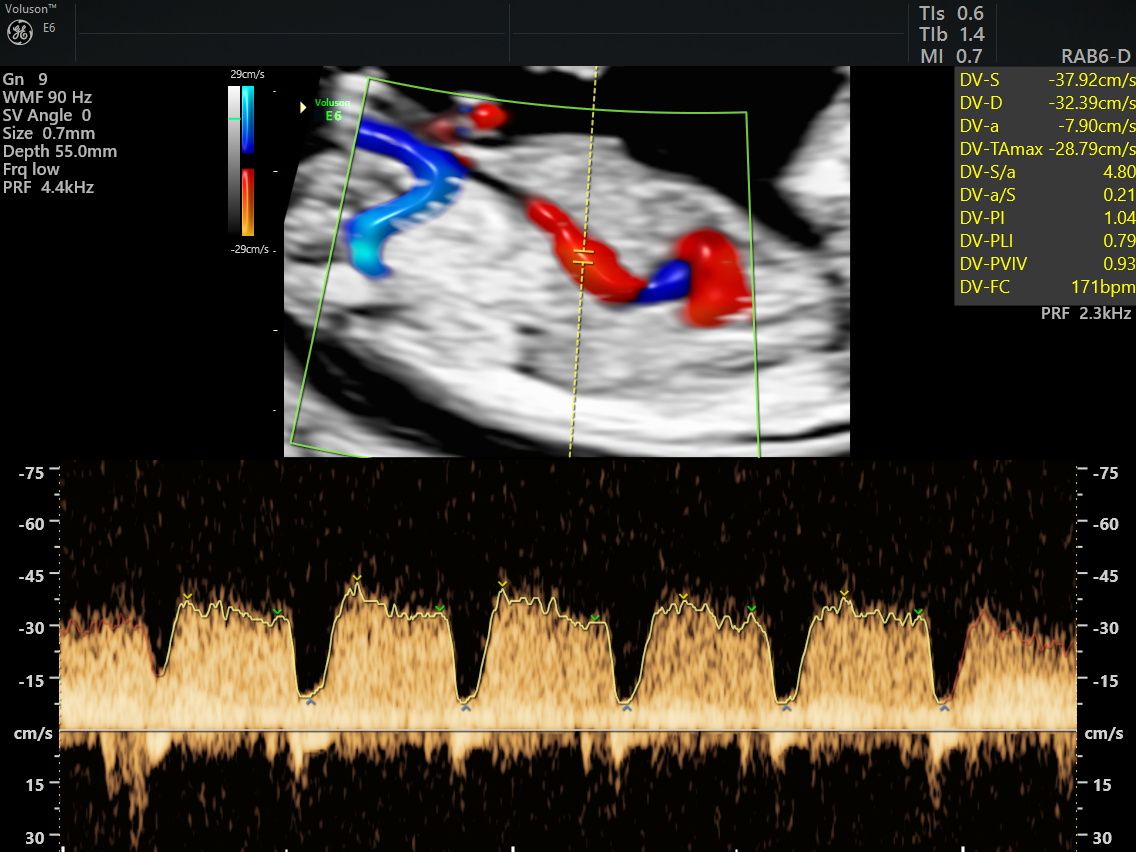

Realizo estudios con tecnología avanzada para detectar posibles complicaciones durante el embarazo. Entre ellos se incluyen ultrasonidos de tamizaje en el primer trimestre, ultrasonidos estructurales, seguimiento de embarazos gemelares y pruebas genéticas como ADN fetal, biopsia de vellosidades coriales y amniocentesis, que ayudan a evaluar la salud del bebé y del embarazo.

Fotos y videos